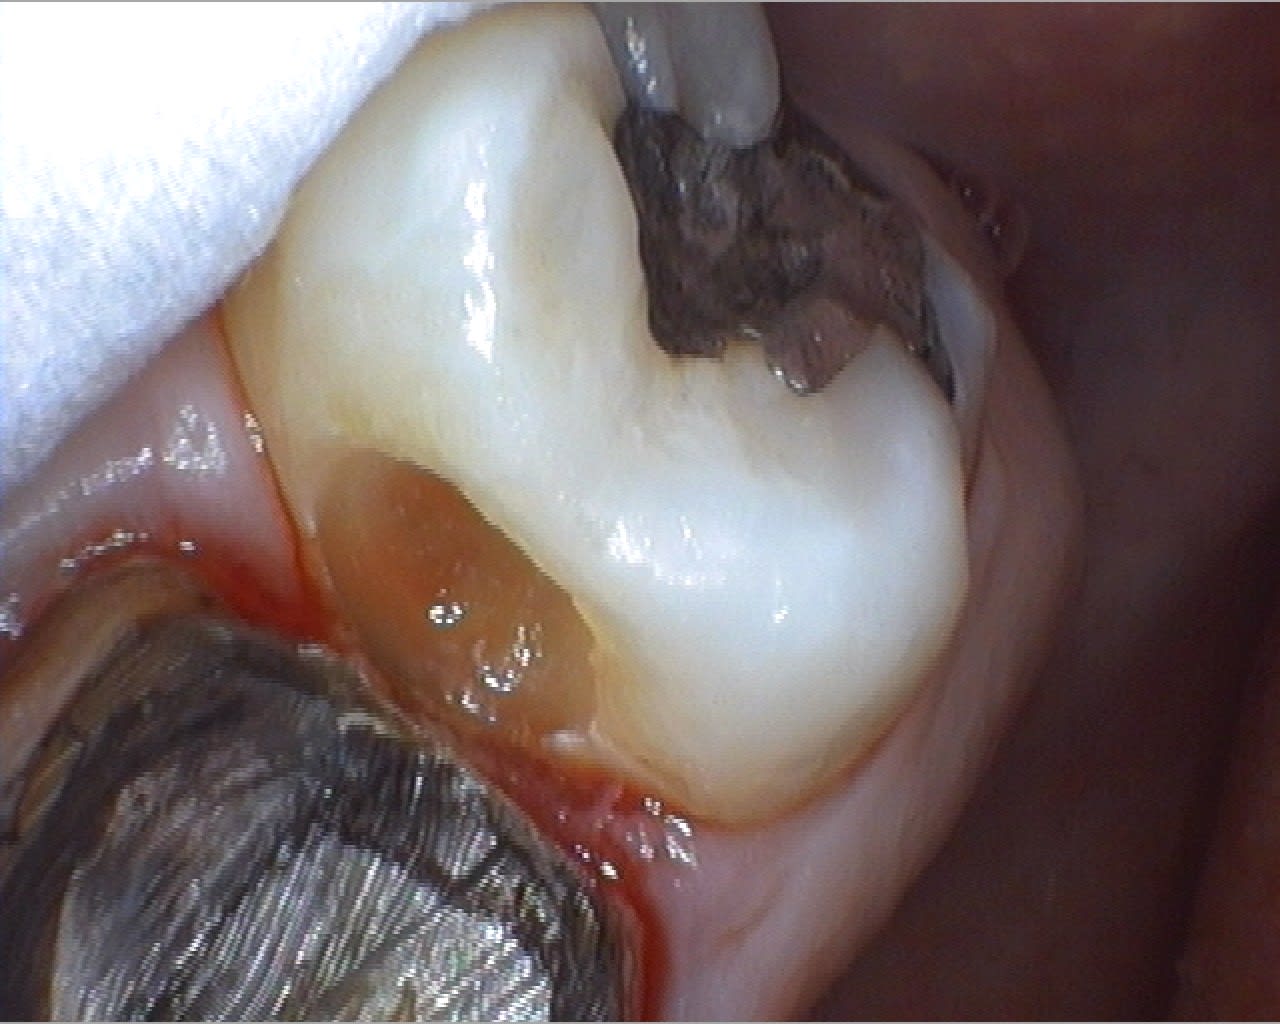

Quelques photos prises ce matin au cours d'une longue séance de soins. Je posterais un test complet de la caméra bientôt pour ceux que ça intéresse...

On est bien d'accord Pluton, c'est de la merde, mais immédiate en acquisition et très pratique pour caser une CCM !

J'ai remonter le post pour un copain nonolien qui voulait savoir comment on gère le double mélange à l'Impregum. Simplement pour montrer le berceau gingival sans saignement.